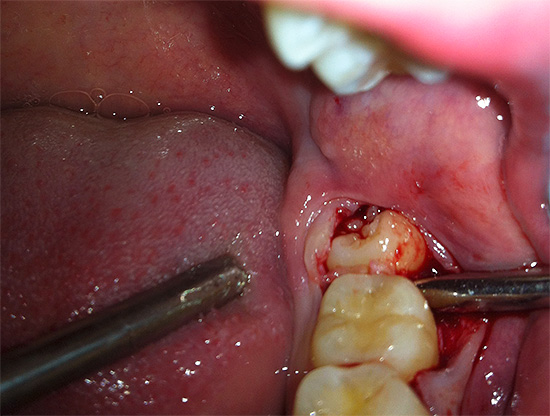

Por isso, antes de executar o procedimento de remoção, pode ser necessário fazer um raio-x de diagnóstico, permitindo que o dentista-cirurgião entenda com o que ele terá que lidar. Isso ajuda a evitar erros por parte do médico e também reduz o risco de possíveis complicações pós-operatórias.

Ao remover o dente do siso, o cirurgião-dentista é frequentemente forçado a recorrer a vários truques e pode usar uma variedade de ferramentas.Muitas vezes, é impossível conviver com uma pinça, para não se surpreender e não se assustar se o médico começar literalmente a cortar seu dente em pedaços ou agarrar o cinzel e começar a bater nele ...